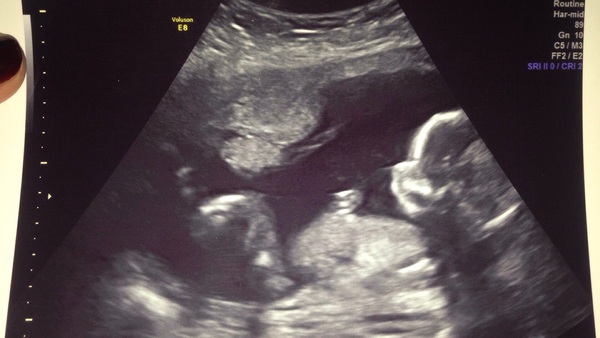

CatEsco7 · 07/05/2016 12:17

Hi October Mums to be! Smile

Anyone want to take a guess on whether it's a boy or girl based on nub theory???

October 2016 (thread number four). Entering the second trimester.